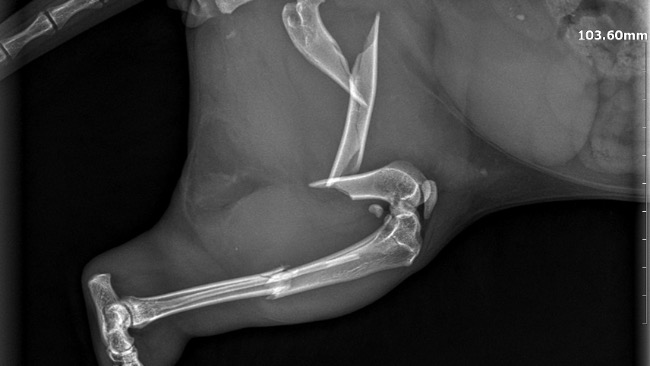

Dziś Pani Ania z Przychodnia Weterynaryjna CapraVet zrobiła zdjęcie rtg łapki. Okazało się, ze ta jest złamana w trzech miejscach 😱Takiego urazu mógł się nabawić tylko w bliskim spotkaniu z pędzącym autem 😢 Filemon niestety przebiegał 32. Tym razem nie zdążył. Na szczęście, choć poturbowany, dotarł na swoje śmieci. Gdyby skrył się gdzieś w krzakach…

Takie złamanie trzeba szybko operować.

Za radą Gosi Pietrzyk napisałam do Przychodni weterynaryjnej Sanatus w Krosinku. Pani Ania mówi, ze są najlepsi. Kazali mi przywieźć Filemona jutro, we wtorek będzie operowany. Koszt operacji to 1.200 zl. Do tego trzeba doliczyć leczenie po operacji, środki przeciwbólowe, potem usunięcie drutów. Stąd ta zbiórka.